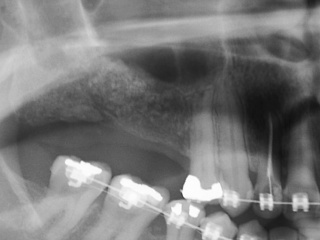

Enxerto de seio maxilar